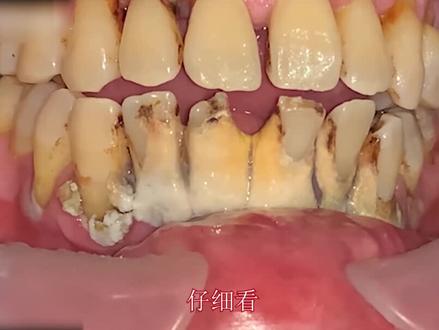

这个小伙实在太懒了,抽了二十多年的香烟都没能养成刷牙的习惯,每次出去相亲,女生看到他这一口大黑牙直呼受不了, 所以小伙只能勉为其难的去洗一次牙齿。只见小伙张开他的血盆大口,映入眼帘的就是一嘴地道的黑色牙结石,就连从业三十年的老牙医看了都佩服不已。牙医将超声波洗牙器塞进小伙的嘴里,在超声波的震动下,一块块细小的牙结石被震动下来。 由于小伙从小就不刷牙,所以牙结石被震下来后,牙齿仍然是黄黄的样子, 看起来就像是玉米粒一般。在牙齿和牙龈的连接处,牙结石就像是老顽固一样,长得十分硕大,奈何碰上了高科技,三下五除二就从扎根了二十年的地方脱落下来。 中间牙齿受灾最为严重,牙医拿着洗牙器不停的滋滋滋,都没能将它扣下来,所以牙医只好换下一颗牙齿操作 表面的黑色菌斑冲洗下来后,一大块牙结石脱落下来,随后立马被吸管吸走,看起来真是太解压了。 没到三分钟的时间,小火口中的牙结石基本都清理干净了,只剩下中间那颗没清理完成的牙齿,看起来是不是很像一个笑脸呢?牙医沿着嘴角处冲洗,顽固的牙结石瞬间四分五裂,明显地方的牙 牙结石清理掉后,牙医又在犄角旮旯的地方完整的清理了一番, 在超声波的作用下,小伙的一口大黑牙被处理的干干净净。看到洗牙前后的明显对比,看来平时不养成良好的刷牙习惯,后果可是让人十分触目惊心的呀!

仔细看这位六十岁的小伙,大门牙正面已经被结石深深的包围,牙齿后面也是漆黑漆黑的,小伙说他每天吃三四包槟榔,吃完一颗槟榔抽一根烟,那种感觉简直快活似神仙,就是有点费牙脱, 你老是打开了心爱的小水枪,水枪所到之处皆是灰飞烟灭,那种酸爽谁起谁知道, 托尼老师一高人胆大,不一会正面的结石就洗不干净,赶紧换到后面,后面的牙齿真的是太黑了,抽烟的朋友应该深有体会。托尼继续表演着他的绝活,黑黑的郊游也在水枪的威力下烟消云散。 一番烧操作,小火牙齿的背面也已经清洗干净, 这样看上去小伙的牙齿是不是非常的漂亮,妥妥的帅哥一枚。